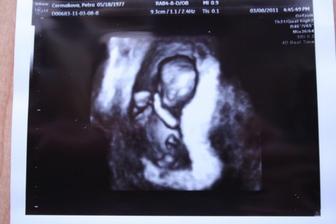

Třetí miminko?

Třetí miminko jsme tedy nikdy neplánovali...stále kojím, MS ještě nepřišla.....no, ale místo ní podivné tušení a nakonec potvrzení. Je hodně brzy, jsem teď nesjpíše 13 DPO, tak uvidíme, jak se bude čárka klubat dál a jestli z čárky bude nakonec i miminko.

Prvotní rozčarování a šok jsou už pryč a na třetí miminko se moc těším (e?)🙂 a starosti hážu za hlavu....však my to nějak zvládneme🙂